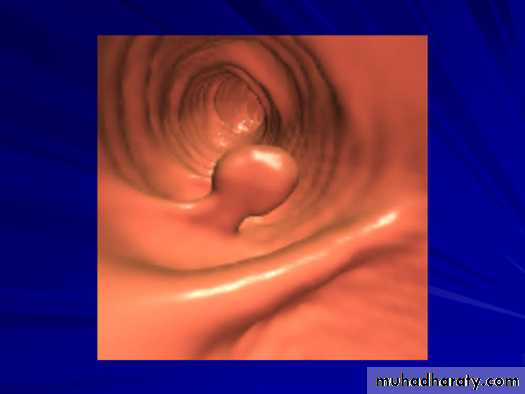

• Colonic Polyp:_Solitary or multiple._Produce small , well-defined rounded filling defect best seen in double contrast enema or post-evacuation enema ._ May be sessile or pedunculated ._ The pedicle appear as two parallel line of filling defect (stalk) and shows change of position with change of posture of patient .Familial adenomatosis polyposis syndrom (FAPS)